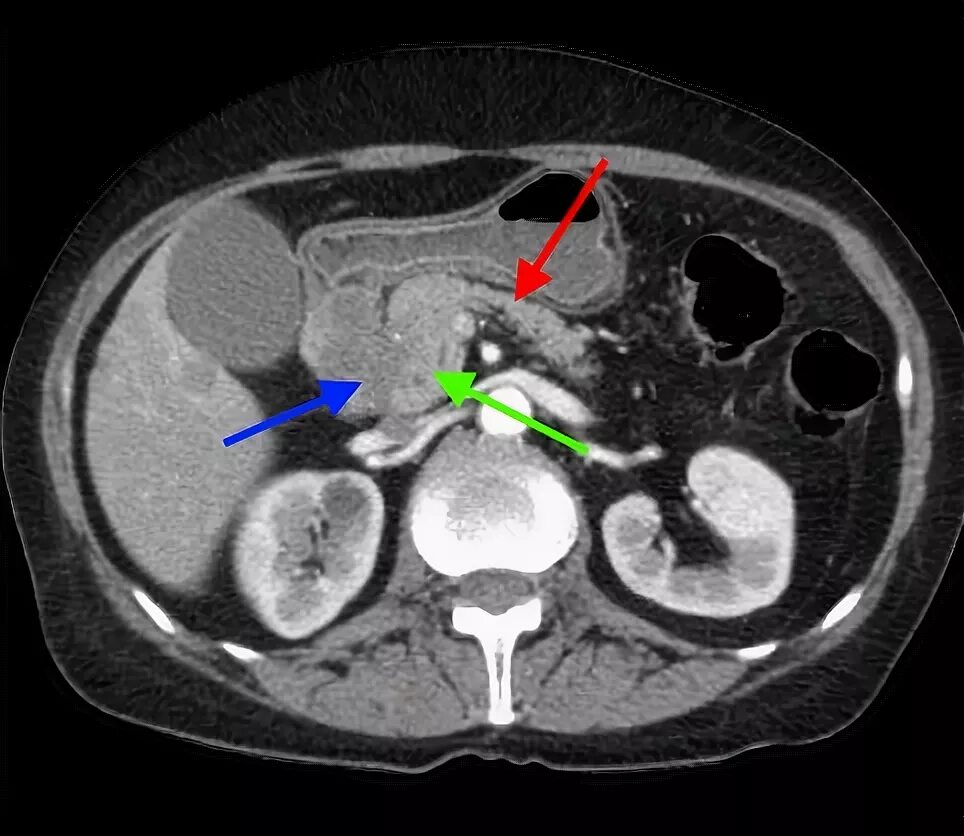

Мрт кисты поджелудочной